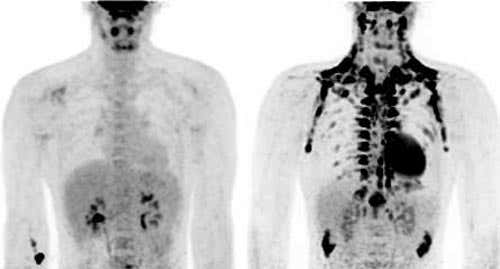

This micrograph image of brown fat showing the extraordinary number of mitochondria involved in heat generation (Image: Laura Austgen and R. Bowen) In this PET-CT scan Brown fat (black) shows up after exposure to cold (right) but is not apparent in a scan at room temperature (left). (Image: W. Van Marken Lichtenbelt)